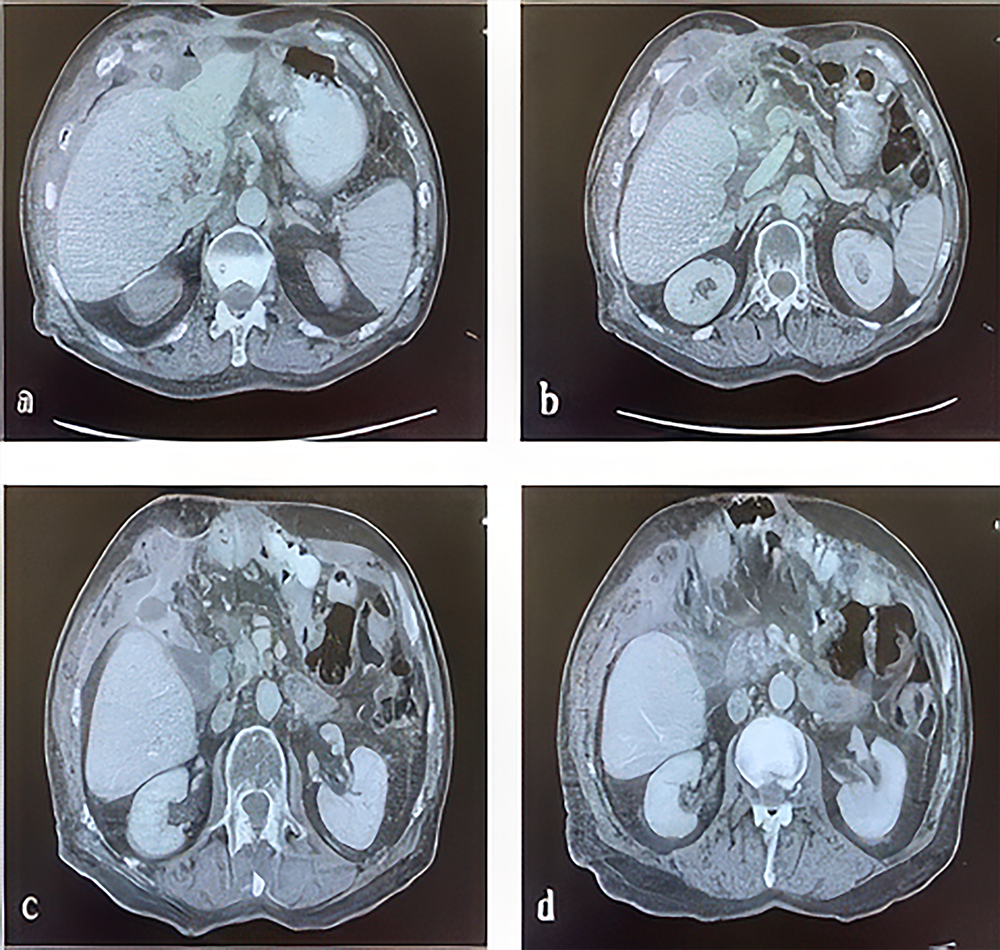

Seven months after the initial intervention, the patient returned with abdominal wall discharge, pain, and fever. Examination revealed purulent discharge from the skin. Abdominal CT confirmed a recurrent perihepatic abscess with enterocutaneous fistulization, similar to the prior episode (Figure 2). The abscess was again localized to the perihepatic region without systemic complications, and DSL was identified as the etiology. The patient was readmitted, and ultrasound-guided 12F catheter drainage was performed. Oral intake was discontinued, and parenteral nutrition with intravenous antibiotics was administered. The catheter was removed on day 15 after the procedure, the fistula was repaired, and the patient was discharged in stable condition on day 36. At the one-month follow-up, no acute pathology was observed, and the patient’s condition remained stable.

Figure 2. Abdominal CT imaging sections obtained after the patient’s presentation, showing images of an abscess and enterocutaneous fistula